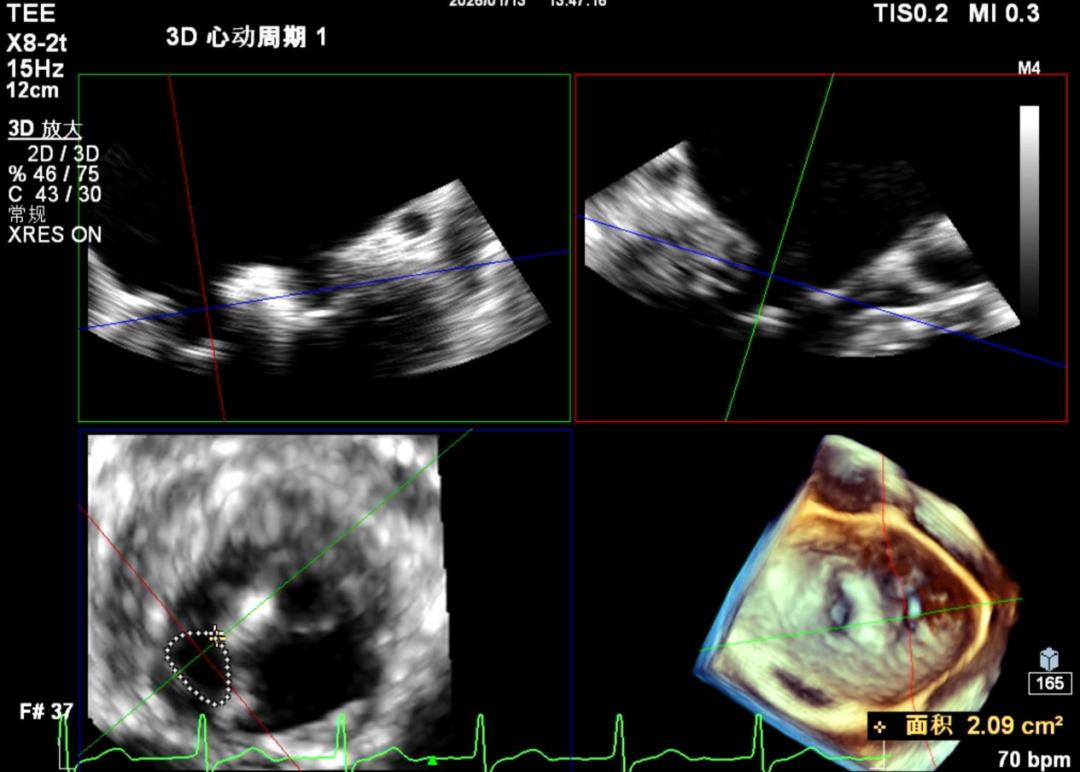

3D

怎么上穿刺鞘攻克巨大左房伴转位穿刺难关!温医大附一院周浩教授团队创新应用“导丝定位+可调弯鞘”技术完成高难度TEER手术_https://www.jmylbn.com_新闻资讯_第9张

3D带彩

怎么上穿刺鞘攻克巨大左房伴转位穿刺难关!温医大附一院周浩教授团队创新应用“导丝定位+可调弯鞘”技术完成高难度TEER手术_https://www.jmylbn.com_新闻资讯_第10张

1.二尖瓣重度关闭不全(4+),瓣环明显扩大(AP径4.6cm,LM径3.9cm),扁平,关闭时瓣叶对合不佳(carpentier I),1-3区均可见反流束,返流宽度达26mm;肺静脉频谱呈收缩期反向。

2.画迹法测得二尖瓣瓣口面积约8.8cm²。

3.PISA法测得EROA=0.57cm²,Rvol=77ml,r=11mm。

4.二尖瓣前叶(A2)长度29mm,后叶(P2)长度11mm。

5.左房巨大(三径86*84*114mm),右房巨大(内径114*86mm),CFI提示极重度三尖瓣反流,Teich法测得EF为70.1%。